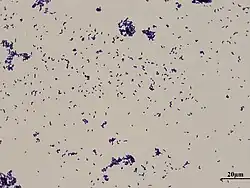

| Gram stain of Corynebacterium xerosis | |

Corynebacterium xerosis is a gram-positive, rod-shaped bacterium in the genus Corynebacterium. Although it is frequently a harmless commensal organism living on the skin and in the mucous membranes, C. xerosis is also a clinically relevant opportunistic pathogen that has been attributed to many different infections in animals and humans.[1][2] However, its actual prominence in human medicine is up for debate due to early difficulties distinguishing it from other Corynebacterium species in clinical isolates.